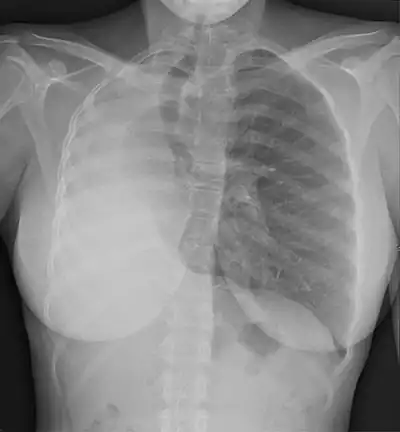

Pulmonary hypoplasia is incomplete development of the lungs, resulting in an abnormally low number or small size of bronchopulmonary segments or alveoli. A congenital malformation, it most often occurs secondary to other fetal abnormalities that interfere with normal development of the lungs. Primary (idiopathic) pulmonary hypoplasia is rare and usually not associated with other maternal or fetal abnormalities.